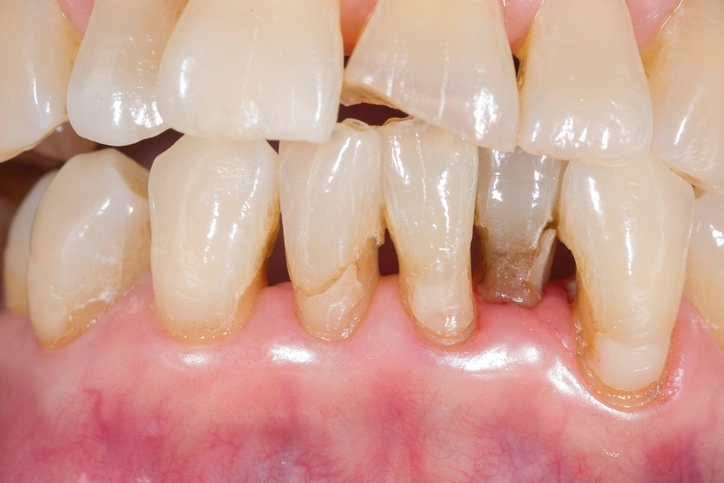

2. Aesthetic Deterioration

Aesthetic failure is especially relevant for anterior restorations. Causes include:

- Staining from dietary chromogens (coffee, wine, tea, tobacco)

- Surface wear leading to roughness and increased plaque retention

- Color mismatch due to aging of composite resins

- Darkening of underlying dentine or corrosion products from metal alloys

1. Failed Aesthetics

Aesthetic failure refers to visual or cosmetic defects that may or may not correlate with functional issues. Examples include:

- Discoloration of underlying dentine: Often seen with older amalgams or in cases of pulp degeneration

- Surface staining: Typically caused by dietary or lifestyle habits

- Mismatch of restoration color: Aged composites may lose their translucency or yellow over time

- Surface roughness: Exaggerated wear or improper finishing